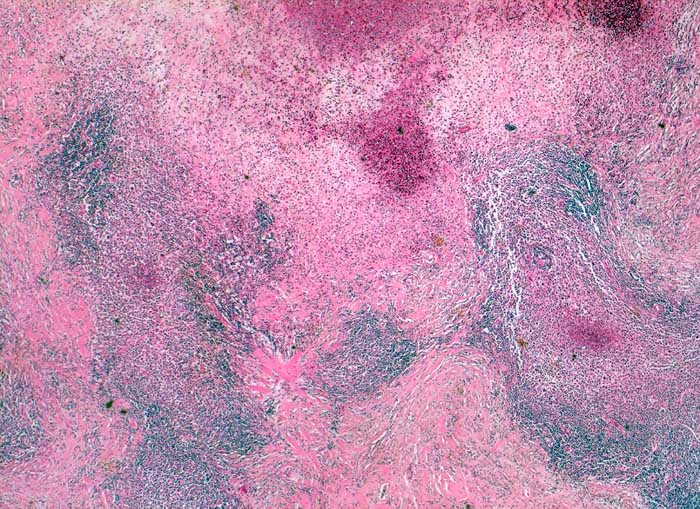

Das Zellbild ist bunt und umfasst Lymphozyten, Plasmazellen, eosinophile Granulozyten und einzeln im reaktiven Infiltrat liegende Tumorzellen. Die Tumorzellen sind einkernig (Hodgkin Zelle) oder mehrkernig (Reed-Sternbergzellen) und enthalten einen sehr grossen Nukleolus. Die Tumorzellen sind immunzytochemisch positiv für CD15 und CD30. Nodulär sklerosierender und gemischtzelliger Subtyp des Hodgkin Lymphoms sind zytologisch nicht sicher zu unterscheiden.

Gezeigt werden eine noduläre Sklerose und zwei Hodgkin Lymphome vom Mischzelltyp.